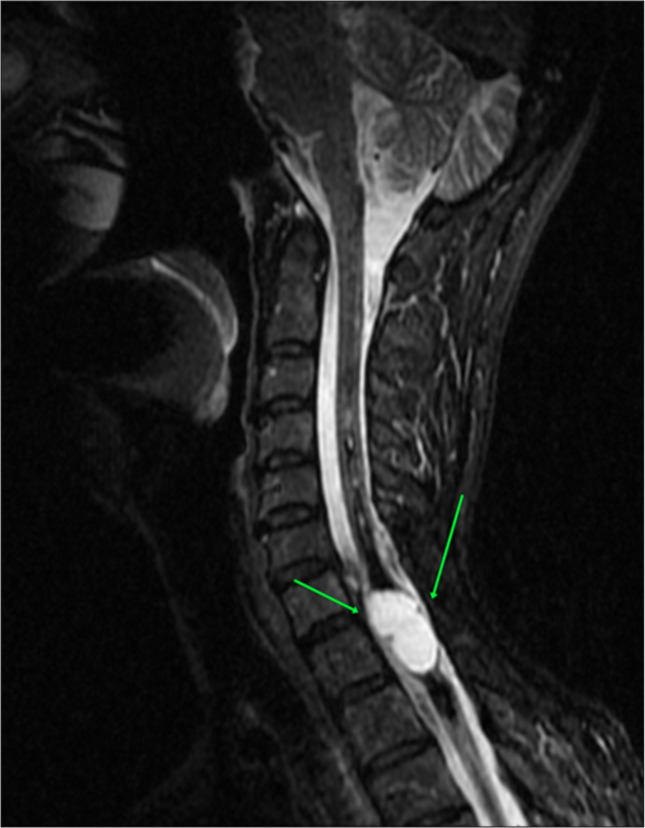

Syringomyelia is a rare condition characterized by the formation of a fluid-filled cyst within the spinal cord, leading to myelopathy. In addition, the pathological enlargement of the central canal is referred to as hydromyelia or cleft-like syrinx. We present a case of idiopathic syringomyelia and hematomyelia in a 50-year-old female patient with a 5-year follow-up on her disease progression. Magnetic resonance imaging (MRI) images revealed low-signal intensity on T1 and high-signal intensity on T2, with elevated hemorrhagic signal intensity on T1 and low peripheral signal intensity on T2. A fluid-filled lesion measuring 12 × 36 mm was observed between the C7 and Th3 vertebrae, with separation from some of the detailed components. No contrast enhancement was noted following IV contrast administration. Based on the MRI findings, a diagnosis consistent with giant hemorrhagic syringomyelia was established. Subsequently, a neurosurgical intervention was performed, resulting in a reduction in the size of the syringomyelia and a moderate improvement in the patient's symptom profile.